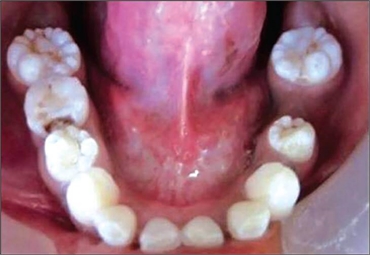

With mulberry teeth, the first molars are dwarfed by small occlusal surfaces and often have disorganized globular projections. The roughened surfaces of teeth is reminiscent of mulberry fruits with many small bumps, hence the name.

Mulberry teeth are uncommon. But the condition is easily recognizable and dentists should be able to identify it as soon as the bumpy surface of the teeth has been noted. Then dentist may suggest a blood test to confirm Syphilis. The test checks for a specific antibody produced in people with the condition. And because the antibodies that fight Syphilis can remain in the body for years, the physician can tell if a patient was ever infected—even if it was a long time ago.

With mulberry teeth, the bumpy surface of the tooth increases the risk of cavities. For this reason, many dentists recommend crown restorations for mulberry teeth. Dental crowns will help strengthen teeth and improve aesthetic appearance. It is important to speak to a dentist about which treatments might work best.